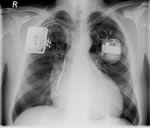

Elektrische Implantate bei Herzinsuffizienz (Herzschwäche)

Implantation - problemlos? Stecker, Elektroden, Kondensator, Aggregat-Größe, Systemlaufzeit?

Der implantierbare Defibrillator lebenserhaltende Therapie